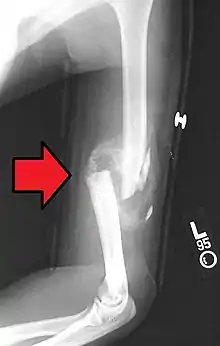

A transverse fracture of the humerus shaft